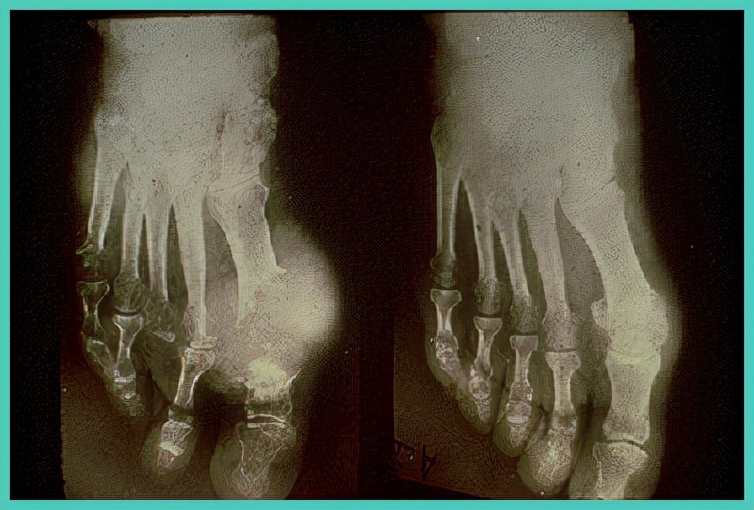

痛风石可以通过直接影响关节或关节肌腱产生显著的关节运动受限,还会逐渐破坏骨质、造成残疾。尿酸盐晶体最初在滑膜、软骨、骨骺的表面形成,然后垂直植入深部,使晶体沉积于骨髓质中央管(哈弗斯管)等处,引起软骨下骨质吸收破坏、囊状改变,甚至穿凿样损害。

外部看到痛风石,片子看出内部骨质已经没了